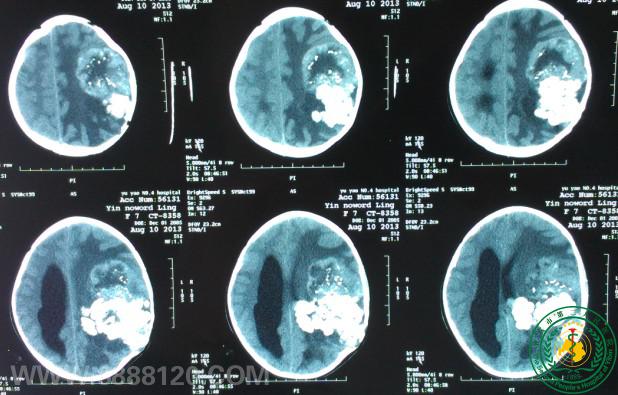

头颅CT示:左侧额颞顶巨大肿瘤占位,大面积钙化,颅骨明显侵犯。我科完成儿童颅内半球巨大室管膜瘤一例